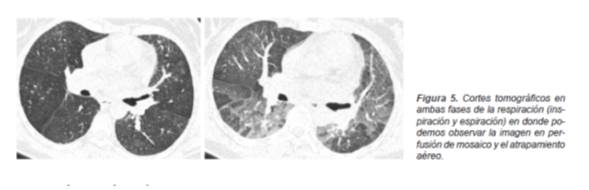

Además de los patrones específicos para el tipo de afección intersticial, contamos con las imágenes que identifican a las alteraciones a nivel de la vía aérea. Son signos indirectos de la obstrucción bronquiolar la presencia en fase inspiratoria de una imagen en «perfusión en mosaico» mientras que en la fase espiratoria se presenta «atrapamiento aéreo» (11) ,que con frecuencia tendrán una distribución lobulillar (Figura 5).